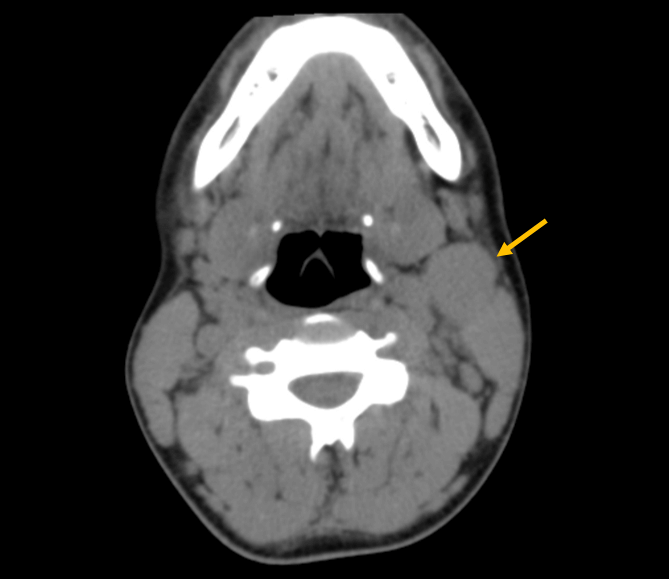

A 14-year-old boy, with a previous history of allergic rhinitis, presented to the PED due to sudden onset of a left cervical swelling. He had a six-month history of dry cough and for the last three days he had also been complaining of dyspnoea and thoracalgia (sudden onset during sleep), which was worsening and now radiating to the right shoulder. No other signs or symptoms. On examination, there was a mass on the anterior left cervical triangle, with approximately 2x3 cm, fixed to the muscle below, firm and non-tender. Laboratory studies revealed normal hemogram (hemoglobin 14.8 g/dL, leucocytes 9.3x1^3uL, neutrophils 68.2%, lymphocytes 21.6%) and elevated C-reactive protein (3.28 mg/dL, N<0.5 mg/dL) and lactate dehydrogenase (1113 U/L, N<230 U/L). The chest x-ray showed a large mediastinal mass (Figure 1) in the middle mediastinum, with a 15.13 cm width, prompting an urgent referral to Oncology. CT scan revealed several lymphoid masses, cervical bilateral (the largest on the left, 4x3 cm) (Figure 2) and at the anterior mediastinum (8.5x5.5cm, 7.5x4cm) (Figure 3). Abdominal CT was normal.

Figure 2. Cervical CT scan: left cervical lymphoid masses (the largest on the left, 4x3 cm).